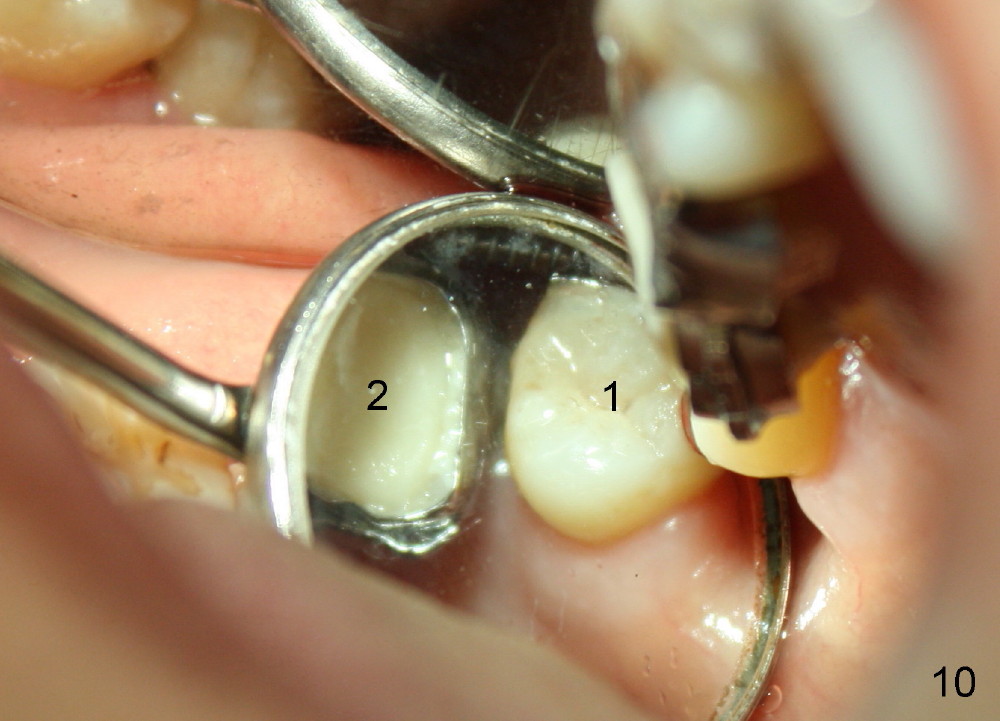

A 48-year-old lady is a dental phobic and has generalized chronic periodontitis. Bone loss around the tooth #2 has been severe for the last 5 years (Fig.1,2 *). Finally she agrees to have #2 (symptomatic) extracted and immediate implant placed (Fig.3 I). A 7x17 mm implant has to be used to achieve primary stability. The remaining buccal and lingual gaps are filled with allograft and membrane (Fig.4 *). Fig.5 shows that there is a space between the tooth #1 (asymptomatic) and the immediate implant (I). The wound/socket is protected by applying perio dressing around an abutment (Fig.6 A). Postop the patient is pain free; the perio dressing dislodges by itself. She returns 3.5 months later for restoration; but the tooth #1 has shifted mesially (Fig.6 arrow). The patient is not so willing to have #1 removed. Bands and bracket are placed in the neighboring teeth including a provisional crown to move the shifted tooth (with mobility) distally (Fig.7,9). The 2nd reason for #1 shifting is abnormal occlsual scheme on the right posterior region (Fig.8); mobility of #1 is the 1st one. The 3rd one is probably bruxism. In 5-6 weeks, the tooth #1 has moved to a desirable position (Fig.10, as compared to Fig.3,5). There is enough space for restoration (Fig.11,12).

In all, posterior immediate provisional should have normal proximal contact so that the neighboring periodontally affected teeth do not shift while the implant is osteointegrating. In order to avoid fibrointegration, the occlusal contact should be off. The patient requests an immediate provisional for the next implant. The same restoration will be fabricated for an implant at a healed site.